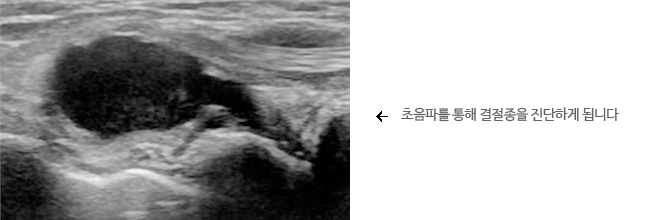

진단은 기본적으로 혹이 생긴 위치와 모양을 진찰하게 됩니다. 대부분 타원형이나 원형으로 부드럽거나 매우 딱딱합니다. X-ray 검사와 초음파를 통해서 확진 할 수 있습니다.